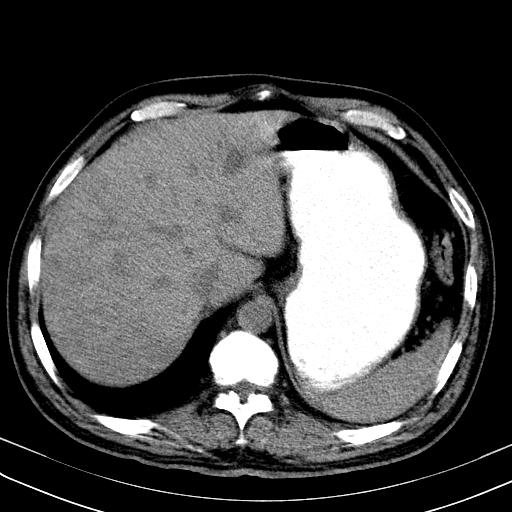

先行ct平扫,纵膈内多发软组织影,ct值约为36hu,以下为增强扫描和腹部平扫。

大家看看肝脏右叶片状低密度影是什么改变啊?

淋巴瘤?肝脏请增强后说啊

多发肿大淋巴结影,肝内改变需结合强化观察

多发肿大淋巴结影,肝内改变需结合强化观察。